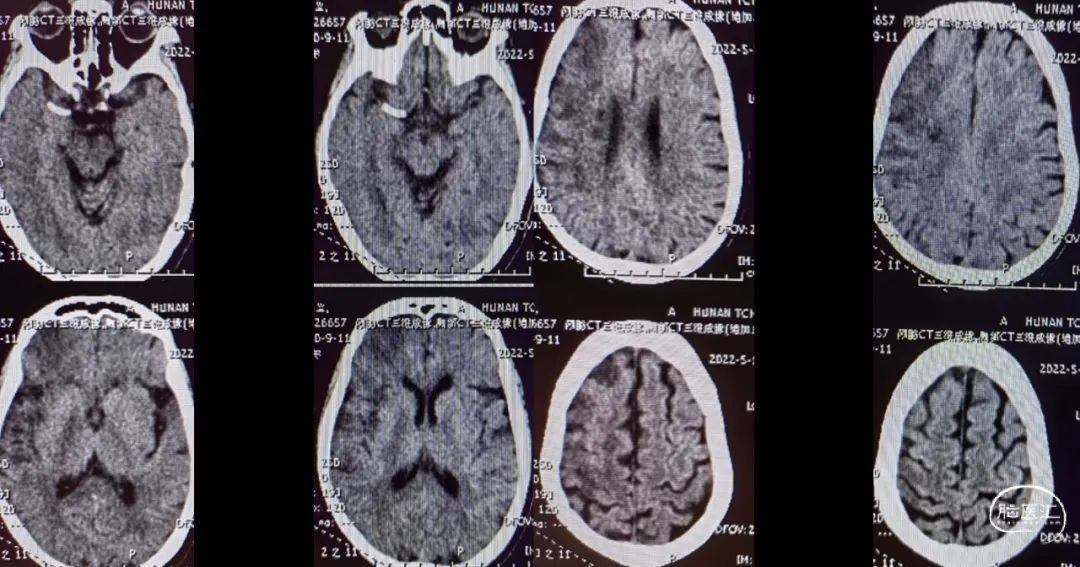

入院影像检查

MRA

重要影像结论:右侧大脑中动脉M1段局限性狭窄。

DWI

重要影像结论:右侧额颞枕顶叶多发急性期脑梗死灶。